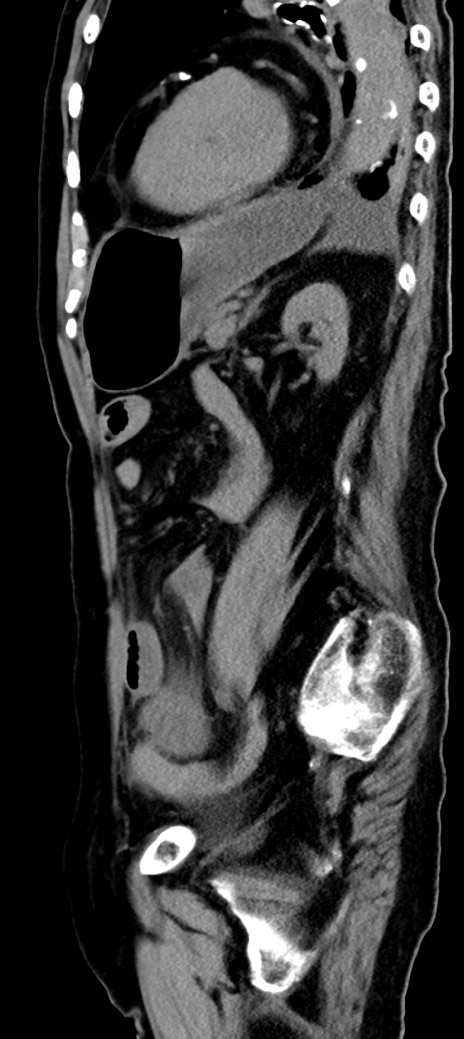

冠状断像